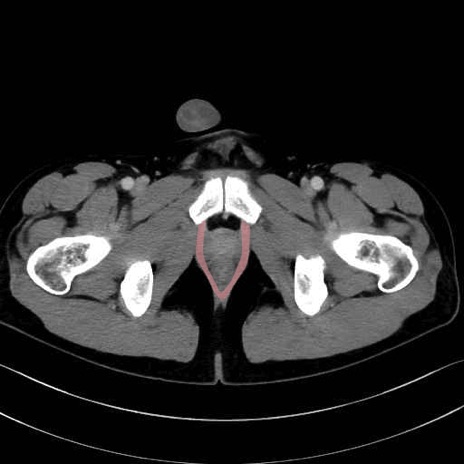

肛門挙筋(levator ani muscle)のCT画像の解剖

肛門挙筋 (Levator ani)